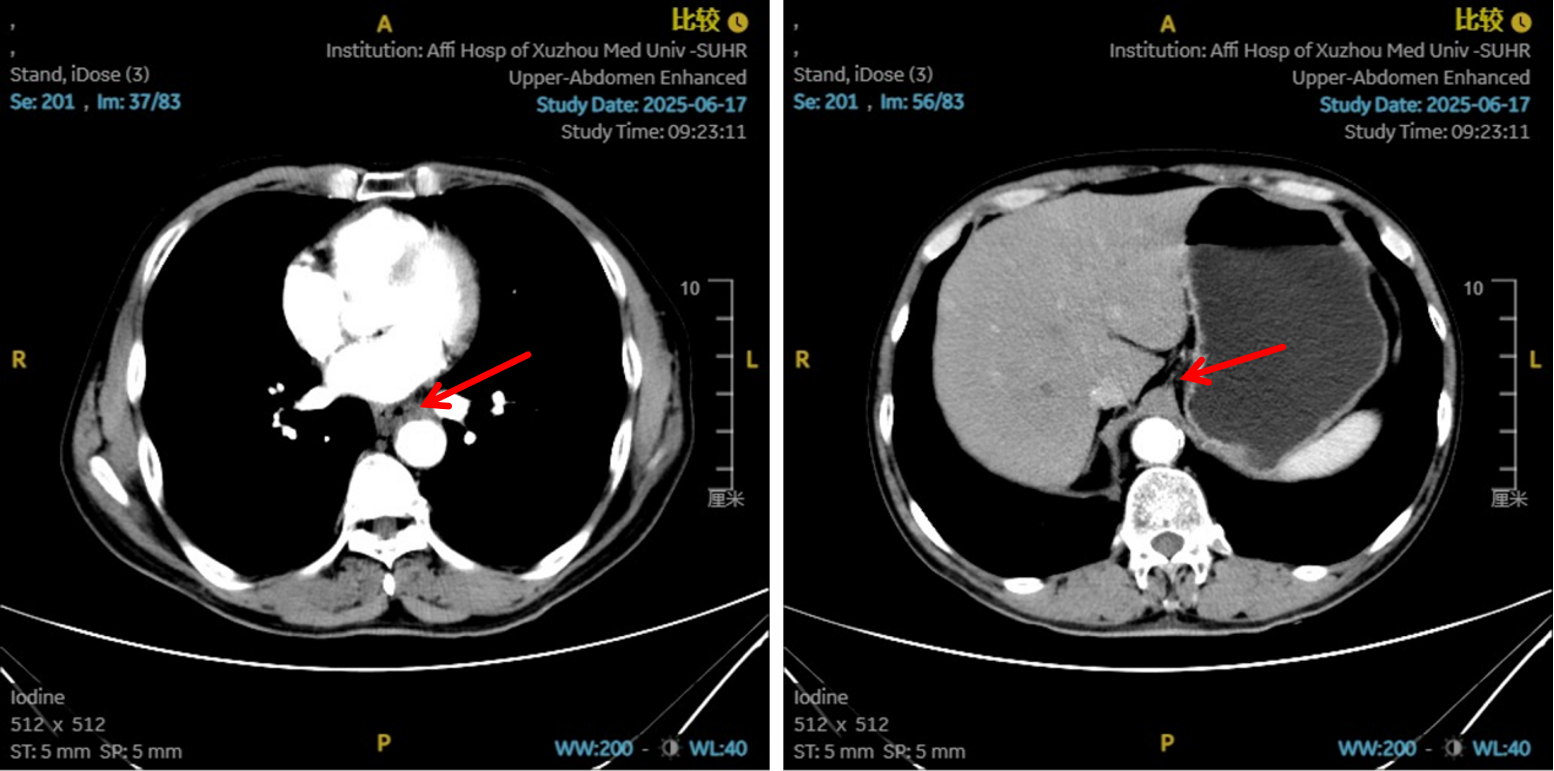

图5:4、6周期化免靶后食管癌病灶对比

图6:4、6周期化免靶后淋巴结对比

图8:6周期治疗后影像学 [图左:“食管Ca化疗后”,食管胸中下段管壁增厚,较厚处管壁约10mm,边缘模糊,病灶局部与邻近大血管、气管壁分界不清。图右:纵隔内(3P、4、7)示小淋巴结影。]

疗效评估

治疗2周期后,食管壁厚度由17mm降至15mm,淋巴结由18mm×15mm缩小至16mm×13mm;4周期后,食管壁进一步缩至12mm,淋巴结明显减少;6周期后,食管壁仅余10mm,纵隔内仅见小淋巴结影,疗效评估“接近CR”。